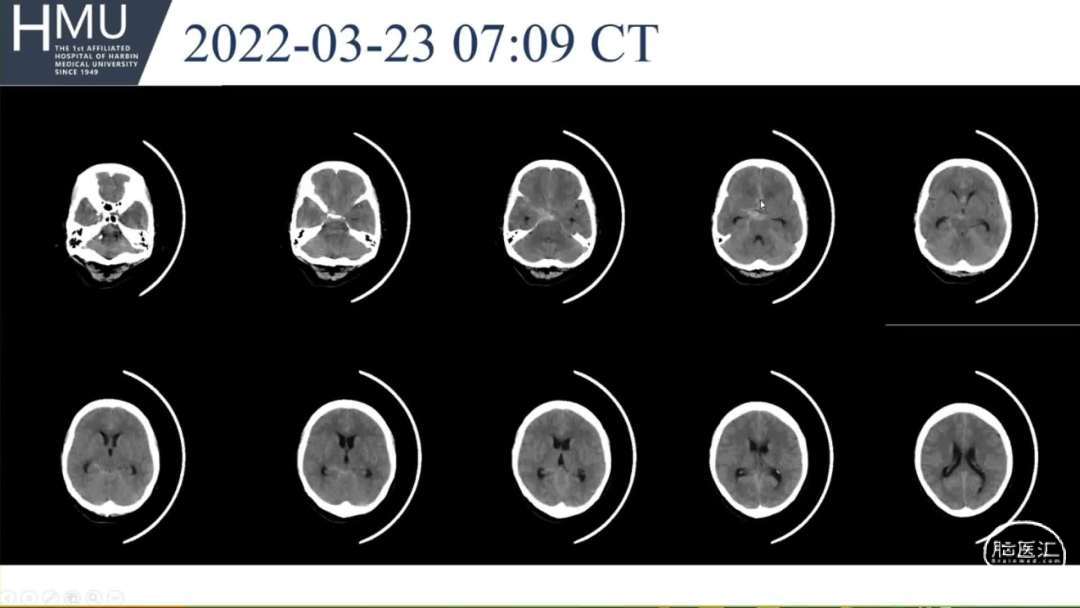

23日06:00

患者答非所问,查体不配合

急行头部CT